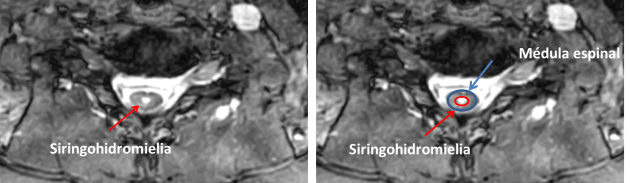

Imagen de una cavidad siringohidromiélica. En azul la médula. En rojo la cavidad

La siringohidromielia (ver imagen arriba) se asocia con la malformación de Chiari tipo I entre el 30-70% de los casos. Se prefiere el término siringohidromielia que incluye tanto el término hidromielia como siringomielia. Hidromielia significa canal central dilatado mientras siringomielia significa cavitación de la médula que se extiende lateralmente o independiente de la cavidad central. El término siringobulbia se refiere cuando la siringohidromielia se extiende al bulbo.